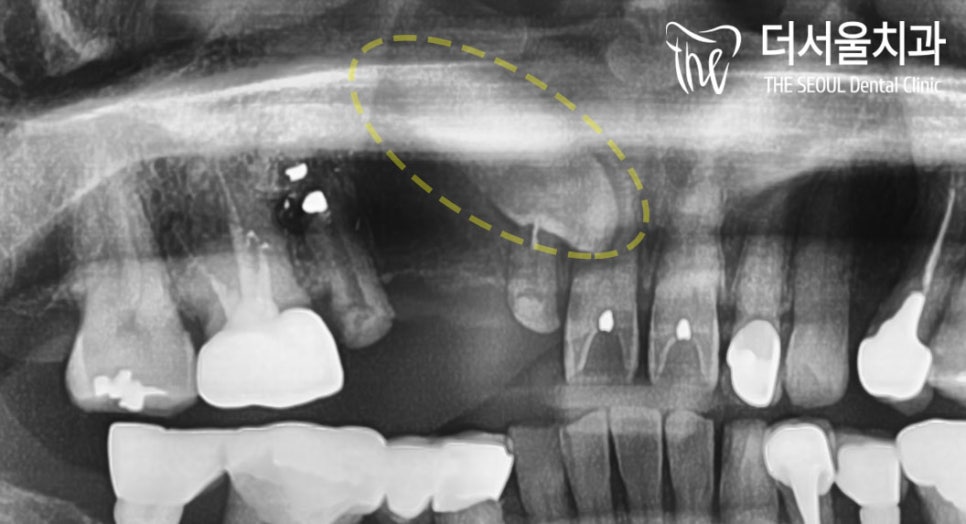

원래 있어야 될 위치에 있지 않고

잇몸 속, 입 천장에 묻혀 있는

말썽꾸러기 같은 곳이 있습니다.

바로 ‘ 매복치아 ‘ 죠.

인접치 뿌리에 가까이 있기 때문에

자칫 잘못하면 신경을 건드릴 수도 있죠.

이분은 # 12 – # 15가

브릿지로 연결되어 있었는데요.

짐작하건대 매복치아 때문에

이렇게 길~~~~~~~게

연결을 해둔 것 같습니다.